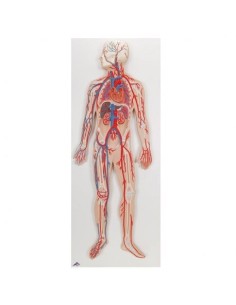

Des modèles anatomiques détaillés pour tous les besoins

Du crâne en 22 parties à verrouillage magnétique aux modèles de colonne vertébrale, des modèles d'articulation aux modèles de cœur, chaque pièce de notre collection est conçue pour une immersion totale dans l'étude de l'anatomie humaine. Nos modèles, réalisés à partir de scans d'os réels, garantissent une expérience tactile authentique et une fidélité de poids presque identique aux originaux.

Indispensables aux étudiants comme aux professionnels, nos modèles anatomiques sont des outils pédagogiques qui permettent d'observer les structures anatomiques avec précision, en évitant les dissections ou les études invasives. Ils sont également utiles pour expliquer les pathologies aux patients, ce qui rend la communication plus efficace et permet de gagner un temps précieux.